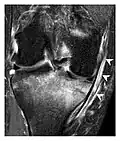

Figure 1: A 56-year-old woman presenting with left knee pain after a fall. (a) Initial anteroposterior radiograph was considered normal, however, subtle cortical disruption of the anterior rim of the medial tibial plateau, medial to the tibial spine, is noted (arrow). (b) Coronal T1-weighted MRI confirms the cortical disruption (arrow) and shows extensive fracture through the proximal tibia. (c) Coronal proton density-weighted image with fat saturation shows extensive edema in the subchondral bone. Note also hypersignal adjacent to the medial collateral ligament corresponding to a grade I sprain (arrowheads).[1]

Occult osseous injuries may result from a direct blow to the bone by compressive forces of adjacent bones against one another or by traction forces during an avulsion injury. Lesions in the tibial plateau, hip, ankle, and wrist are often missed. In a tibial plateau fracture, any disruption of the posterior and anterior cortical rims of the plateau should be sought. Impaction of subchondral bone will appear as an increased sclerosis of the subchondral bone (Figure 1). In the hip, posterior acetabular fractures also present subtle radiographic findings. The acetabular lines should then be carefully examined keeping in mind that the posterior rim, which is harder to see on X-rays, is more frequently fractured than the anterior rim (Figure 2). In the wrist, detection of carpal bone fractures is often challenging, with up to 18% of scaphoid fractures radiographically occult. Carpal fractures, especially the scaphoid, are associated with the risk of avascular necrosis. In apparently normal wrist radiographs from symptomatic patients, if there is history of a fall on an outstretched hand with pain in the anatomic snuffbox, suggesting scaphoid injury, the initial examination with posteroanterior, lateral, and pronation oblique views must be complemented by other specific views such as supination oblique and the "scaphoid" view A careful examination of cortices for evidence of discontinuity or offset and cancellous bone for lucency is necessary (Figure 3).[1]